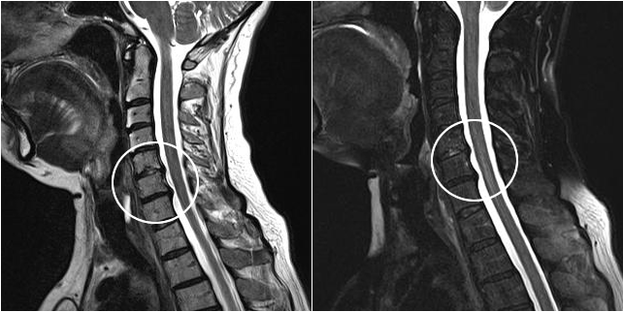

Mezi moderní diagnostické metody patří MRI a CT, které umožňují nejpřesněji vyšetřit procesy destrukce chrupavky a kostní tkáně. Pomocí této techniky je také vhodné diagnostikovat kýly a další defekty měkkých tkání v blízkosti zdroje onemocnění.